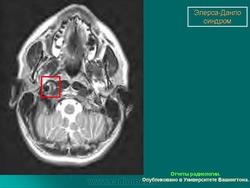

3. Васкулярный тип.

Наследуется по аутосомно-доминантному типу. Основные диагностические критерии: тонкая, прозрачная кожа, разрывы стенки артерий, кишечника и/или матки,обширные кровоизлияния, характерный фенотип. Дополнительные диагностические критерии: гипермобильность мелких суставов, разрыв сухожилий и мышц, косолапость, варикозное расширение вен с ранней манифестацией, артериовенозные каротидно-кавернозные фистулы, пневмоторакс/пневмогидроторакс, атрофия десневого края; положительный семейный анамнез, случаи внезапной смерти у близких родственников (многие пациенты не доживают до 50 лет из-за разрыва артерий или, что реже кишечника). Наличие двух и более главных критериев с большой вероятностью указывает на диагноз васкулярного типа СЭД и является показанием для лабораторной диагностики. Нередко отмечается характерный фенотип (узкий нос, тонкие губы, натянутая кожа, впавшие щеки и экзофтальм, обусловленный, в основном, снижением подкожно-жирового слоя). Надо отметить, что такой фенотип характерен для взрослых больных, а у детей он практически не выражен. Гипермобильность суставов обычно ограничена суставами пальцев. Максимальная частота спонтанных артериальных разрывов приходится на третью-четвертую декады жизни, но они могут возникать и раньше. Чаще всего вовлечены артерии среднего калибра. Беременность и роды могут осложняться разрывом матки и маточными кровотечениями, а также разрывом влагалища и промежности. Именно артериальные разрывы являются наиболее частой причиной внезапной смерти. Поэтому в качестве диагностических мероприятий рекомендуются, по возможности, неинвазивные процедуры. При этом типе СЭД сравнительно хорошо изучены изменения на молекулярно-белковом уровне. Этиологическим фактором являются мутации в гене коллагена IIIтипа.